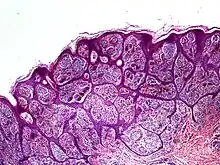

Histology

High-powered imaging tools may identify one or more traits that prove a lesion is a malignant melanoma, rather than a benign nevus:[2]

- Slight pleomorphism of individual cells

- Nuclear atypia with prominent nucleoli

- High rates of mitotic activity (however, some benign nevi also exhibit this trait)[5]

- Penetration through lower tissue layers

In some cases, it may be difficult to identify these features even with a dermatoscope. This is because some nevoid melanomas preserve normal layers of epidermis above them. Excision and biopsy of the suspected lesion can identify nesting, atypical growth patterns, and other hallmarks of malignant growth.[2] In particular, patterns of confluence among melanocytes, parallel arrays of nested cells (parallel theque pattern), and a lack of connective tissue in the lesion should strongly increase suspicion of a malignant nevoid melanoma.[3]